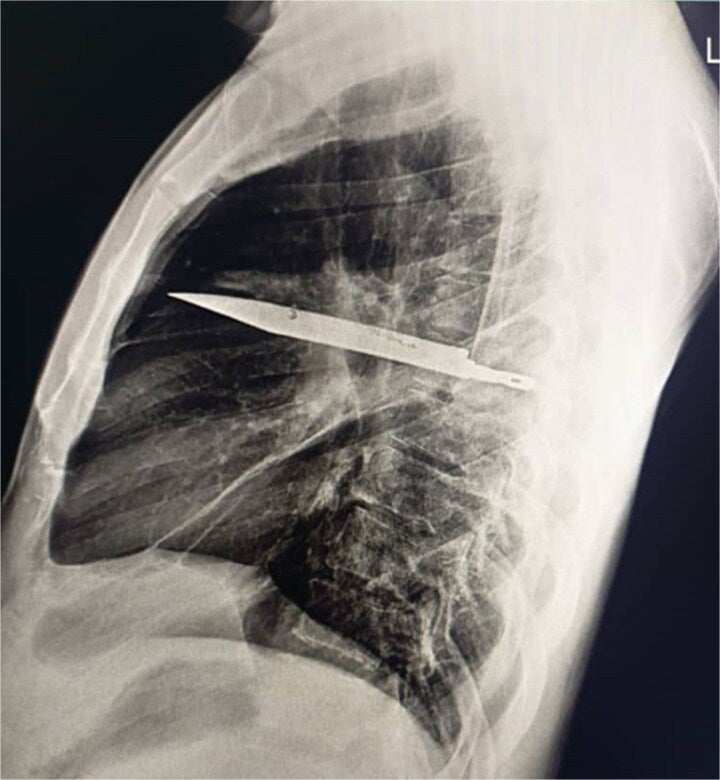

TANZANIA, Africa (WKRC) — Doctors discovered a knife that had been lodged in a man's chest for years after he visited a hospital when his chest began leaking pus.

According to PEOPLE, citing a report from the National Library of Medicine, an unidentified man from Tanzania went to the hospital after noticing his right nipple was leaking pus.

The report states that the man, 44, wasn't suffering from "chest pain, difficulty breathing, cough or fever" at the time of his visit and was "otherwise healthy."

When speaking to doctors at the hospital, the man revealed that he had been "involved in a violent altercation" and had suffered "multiple cuts to his face, back, chest and abdomen."

(WKRC) The report states that the man's body was able to “encapsulate the foreign body within a fibrous capsule, limiting inflammation and tissue damage,” but had began to show "serious complications" when the pus began leaking.